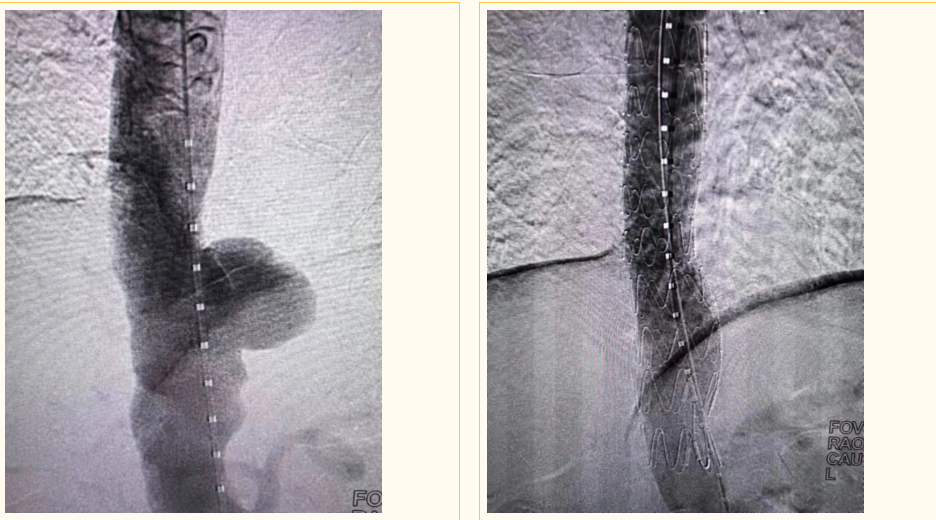

经颈静脉肝内门体分流术(TIPS)作为介入手术中的四级手术,因操作难度大、风险高,被业内誉为介入领域的“天花板”,广泛应用于肝硬化门静脉高压所致的食管胃静脉曲张破裂出血、顽固性胸腹水等疾病治疗。

此前,一名患有5年肝硬化病史的患者,因反复出现认知障碍、腹水加重,进食量与尿量显著减少,在外地医院治疗后效果不佳,为方便后续诊疗且减轻费用负担,转入庆云县人民医院。胸心外普通外科一病区主任医师柳峰、副主任医师张玉良团队对患者病情进行全面评估后,决定为其施行DSA下经颈静脉肝内门体分流术。手术通过颈静脉途径穿刺,在肝静脉与门静脉之间的肝实质内建立分流道,以微创方式显著降低门静脉阻力,从根源上解决门脉高压问题。术后,患者腹水症状明显缓解,认知功能逐步恢复,疗效立竿见影。

该手术对于活动性静脉曲张破裂出血,即刻止血成功率高达90%-99%,一年预防复发出血有效率达70%-85%,能有效减少或消除门脉高压引发的系列并发症。

如今,已累计完成多例复杂TIPS手术,包括海绵状变性、广泛性门静脉血栓等疑难病例,均取得良好治疗效果。